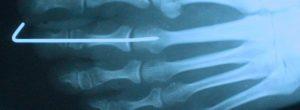

Cirugía de dedo martillo y eliminación de clavos